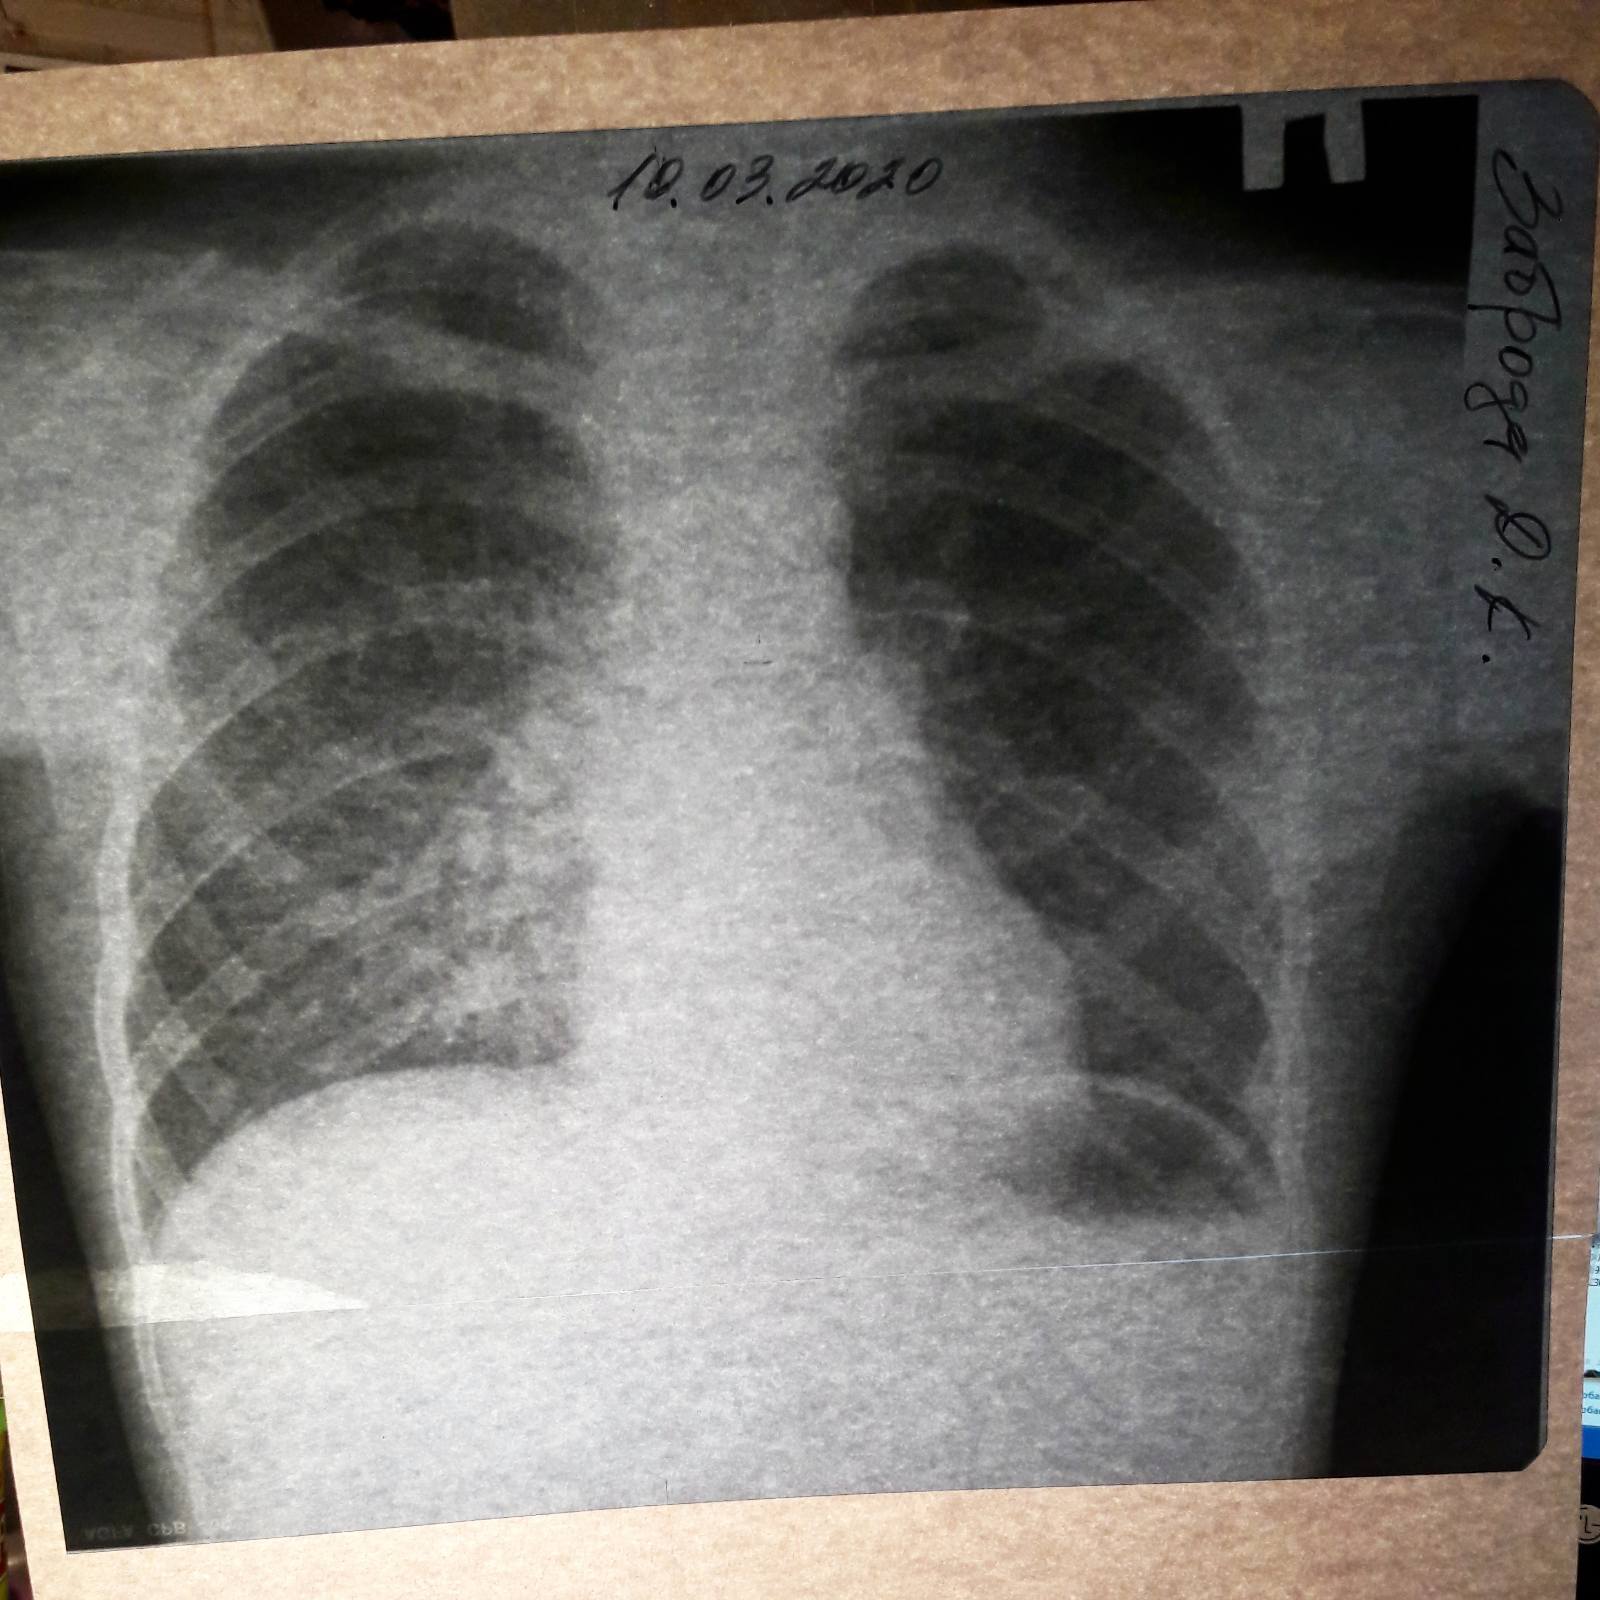

Рентгенодиагностика бронхопневмонии: Советы и примеры

Раздел: Альбом открытий